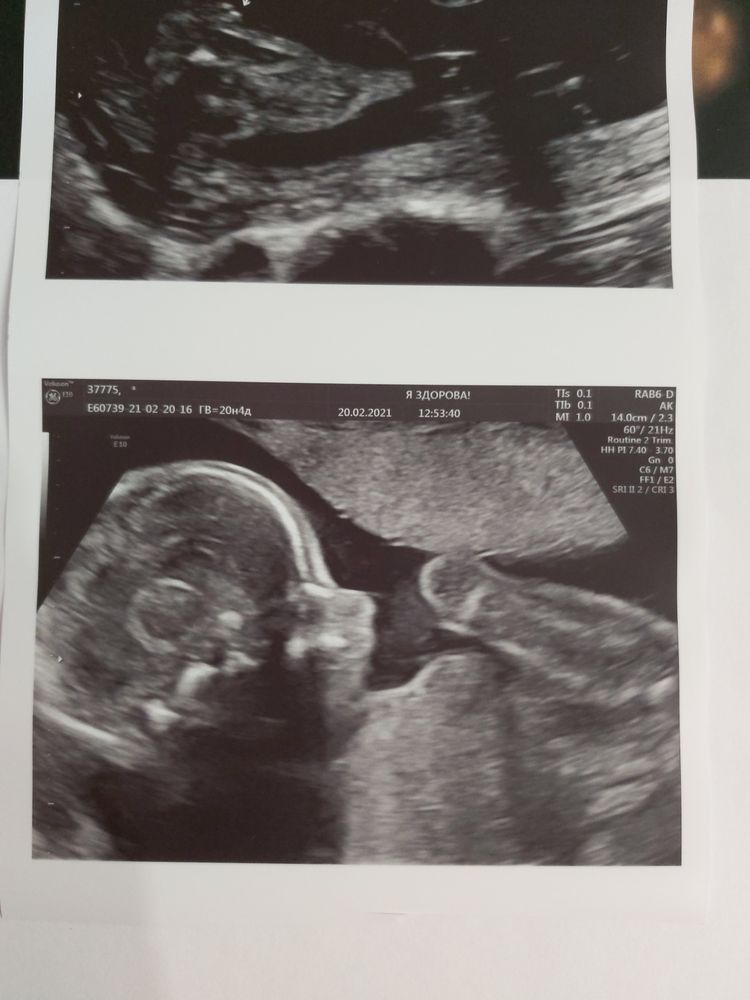

Немножечко фото нашей маленькой врединки🥰